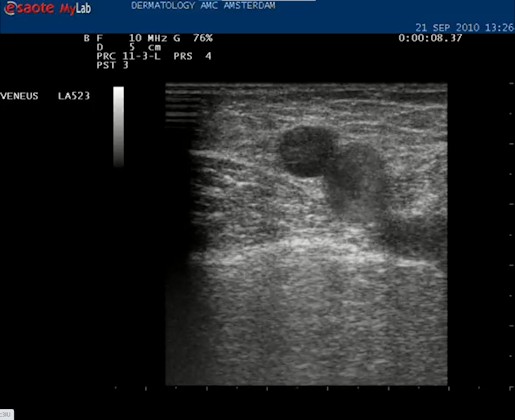

| Met de echokop dwars op de binnenkant van het bovenbeen wordt direct een hooggelegen (extrafasciaal gelegen) vena saphena magna gezien. De VSM wordt in het midden van het beeld geplaatst. |

| Daarna de echokop draaien in de lengte richting van het vat. Nu is het mooi helemaal in beeld. |